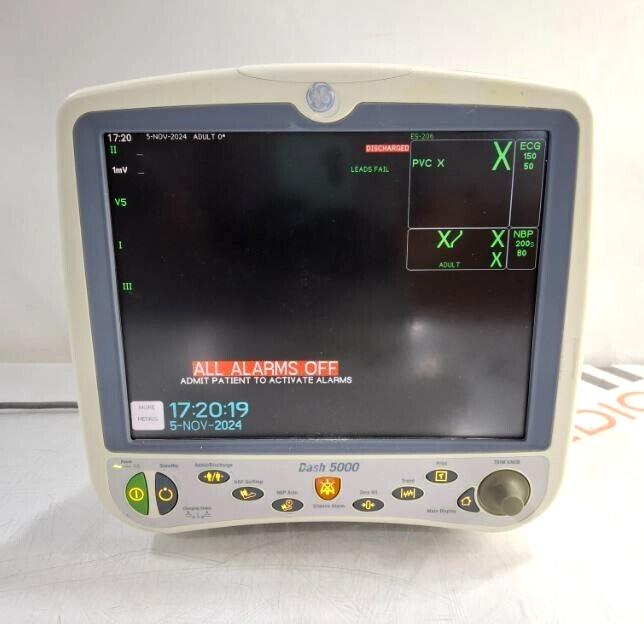

GE Healthcare Dash 5000 - Masimo SpO2 Patient Moni

$217.00

USD

GE Healthcare Dash 5000 - Masimo SpO2 Patient Moni

$217.00

USD

GE Healthcare Dash 5000 - GE/Nellcor SpO2 Patient

$217.00

USD

GE Healthcare Dash 5000 - GE/Nellcor SpO2 Patient

$217.00

USD